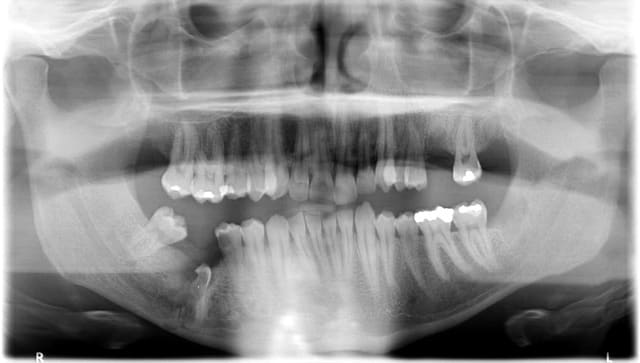

patient adressé au stomato en début d'année pour extraction de 18 28 38 47 46. Je vous montre les 2 panos. implant 26 prevu, doit se décider encore sect 4 sachant que le 45 est a couronner. J'ai revu le patient vendredi 3 mois après l'intervention pour la première fois,qui me dit qu'il n'a plus du tout de sensibilité région mentonnière et cliniquement pas très joli sect 4. Rien de particulier ds le compte rendu opératoire du stomato.

tu peux pas laisser trainer, envoies ca dans un service de maxillo. des lésions périapicales se développent aux apex résiduels, donc il faut vraiment les enlever.

si tu laisse l'os se carapater, la reconstruction par plaques/vis va etre d'autant plus dure...

pour moi il va forcément y avoir une fracture mandibulaire, et ca sera forcément immobilisé sur l'arcade maxillaire par ligatures. donc laisse ca à quelqu'un d'autre. maxillo pour moi, un autre.

pour le patient, les racines résiduelles risquent de poser problème à plus ou moins long terme. c'est pas facile à expliquer au patient, mais il faudrait y retourner avec un bon cone beam préop pour voir exactement quel abord réaliser.

dentascan ou conebeam effectivement, ne serait ce que pour savoir si le NDI a réellement été touché. Ensuite pas évident qu'il faille à tout prix enlever les racines, c'est le reste de couronne qui me gêne plus là. Autant l'os peut venir se reformer au dessus des racines et celles ci rester là à vie sans pb particulier (inutile de penser qu'elle remonteront avec les crochets qu'elles ont au bout et l'ancrage dans l'os basal), autant la partie coronaire qui reste peut éventuellement empêcher cette réossification. Si on ne fait rien (ce que peut préférer le patient, plutôt que de repasser à la moulinette) un ctrl pano à 6 mois, 2 ans et 5 ans pour contrôler qu'une lésion ne se développe pas.

SI j'attends, je ne peux rien faire pour emplacer la(es) dent absente. Le chir doit me rappeler demain.